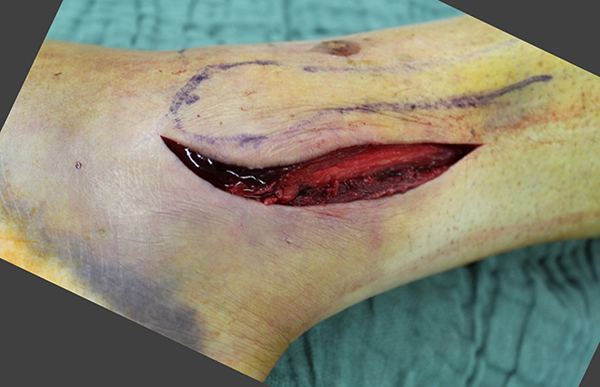

Ein aktuelles systematisches Review zur arthroskopisch-assistierten Frakturversorgung (AORIF) am Sprunggelenk identifizierte bei 495 von 782 Patienten (63,3%) chondrale Verletzungen 54. Weder durch die klinische Untersuchung noch mit konventionellen Röntgenaufnahmen oder mittels CT-Bildgebung lassen sich diese Verletzungen zuverlässig diagnostizieren. Aus diesem Grund rückt die arthroskopisch-assistierte Frakturversorgung am oberen Sprunggelenk zunehmend in den Fokus. Die Arthroskopie ermöglicht im Rahmen der Frakturversorgung sowohl die Kontrolle der Reposition als auch die Beurteilung und Therapie von intraartikulären Pathologien. Während sich die arthroskopisch-unterstützte Versorgung einiger Frakturen bereits etabliert hat (z.B. proximale Tibiafraktur) gehört der Einsatz der Arthroskopie bei der Frakturversorgung des oberen Sprunggelenks in den allermeisten Kliniken noch nicht zum Versorgungsalltag 155 Im Gegenteil, in einer aktuellen amerikanischen Datenbankanalyse des United Healthcare Orthopedic Datasets wurden zwischen 2007 und 2011 insgesamt 32 307 Patienten identifiziert, die mittels ORIF an einer Sprunggelenksfraktur versorgt wurden. In weniger als einem Prozent erfolgte eine arthroskopisch-assistierte Versorgung 55. Dem gegenüber stehen arthroskopische Studien der vergangenen Jahre, die zeigen konnten, wie häufig es zu intraartikulären Verletzungen bei Sprunggelenksfrakturen kommt. Das Risiko für diese intraartikulären Begleitverletzungen nimmt mit der Komplexität der Fraktur zu 5657. Es liegt also nahe, dass bei komplexeren Frakturen die Durchführung einer Arthroskopie im Rahmen der Frakturversorgung einen positiven Effekt auf das Behandlungsergebnis hat. Aus Sicht der Autoren sollte es Ziel für die Zukunft sein, die Frakturtypen zu identifizieren, die von einer arthroskopisch-assistierten Frakturversorgung profitieren. Die diagnostische Arthroskopie mit dem Ziel der gleichzeitigen arthroskopischen Therapie ist in der aktuellen S2-Leitlinie bereits eine Level-1b-Empfehlung. In den Abbildungen 20 – 30 ist schrittweise unser Vorgehen zur arthroskopisch assistierten Versorgung einer Trimalleolarfraktur dargestellt.